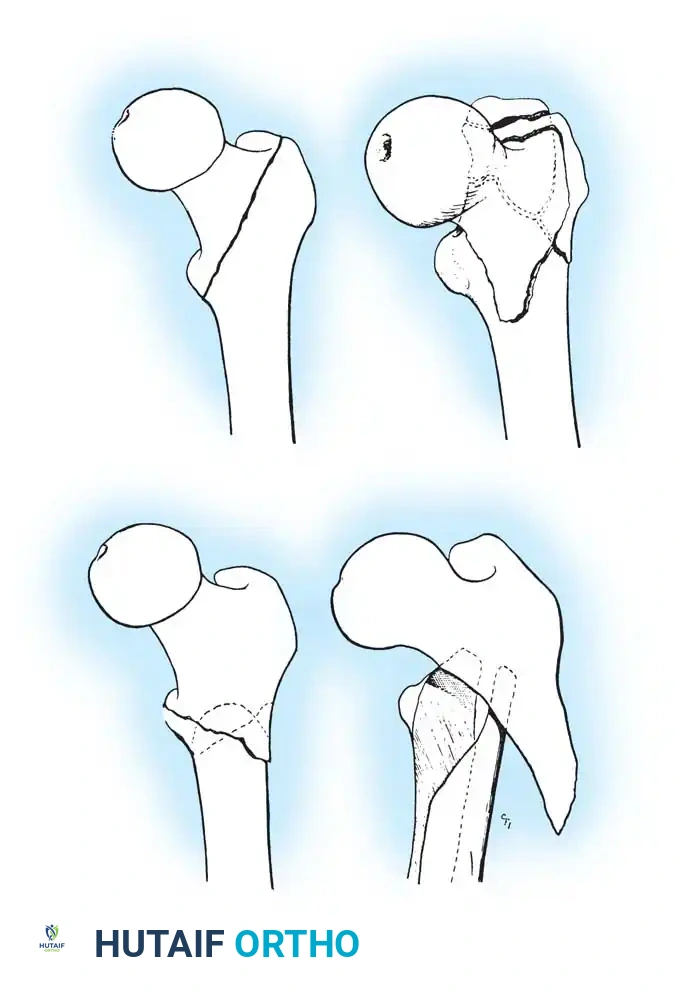

Fig. 52-2: Boyd and Griffin Classification of trochanteric fractures. Types 1 and 2 represent relatively simple patterns, while Types 3 and 4 involve subtrochanteric extension and multi-planar comminution.

- Type 1: Non-comminuted fractures extending along the intertrochanteric line. Simple to reduce and highly stable.

- Type 2: Comminuted fractures along the intertrochanteric line. Reduction is more challenging due to cortical comminution.

- Type 3: Fractures with a subtrochanteric extension. These are inherently unstable and difficult to manage.

- Type 4: Complex fractures involving the trochanteric region and proximal shaft in at least two planes (sagittal and coronal).